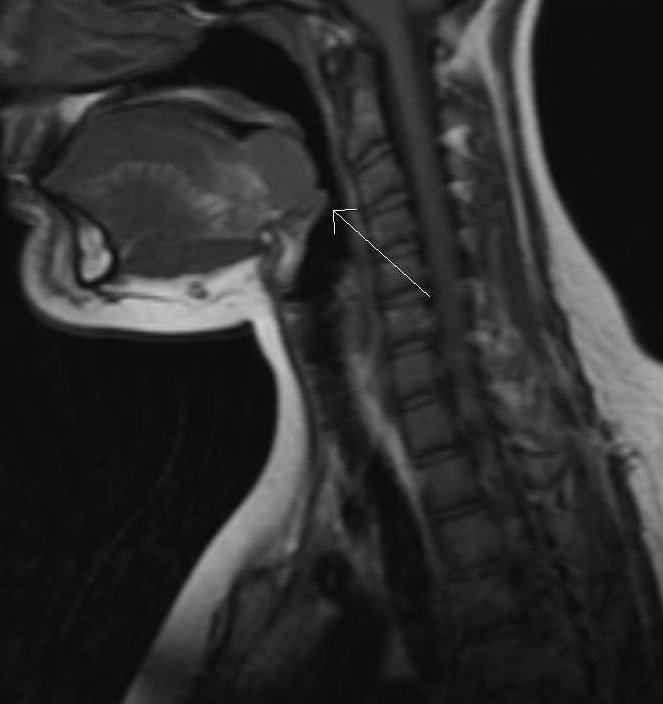

Lingual thyroid is the most frequent ectopic location of thyroid gland  due aberrant embryogenesis during the descent of thyroid gland to the neck.↙️👨🏻‍⚕️👩🏻‍⚕️📚 Prevalence:➡️ 1 in 100000 to 1 in 300000 Lingual thyroid is 4-7 times more common in females. #SoMe4IQLatAm #SoMe4Surgery

Lingual thyroid is the most frequent ectopic location of thyroid gland  due aberrant embryogenesis during the descent of thyroid gland to the neck.↙️👨🏻‍⚕️👩🏻‍⚕️📚

Prevalence:➡️ 1 in 100000 to 1 in 300000

Lingual thyroid is 4-7 times more common in females.